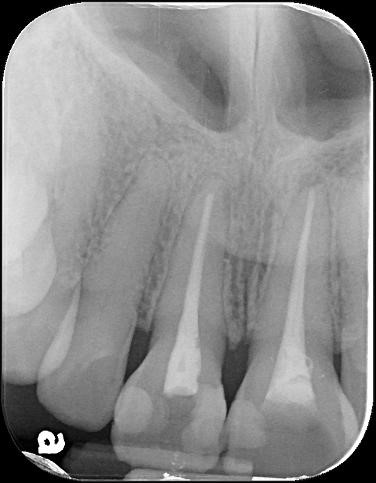

治療後根尖片,密合度良好